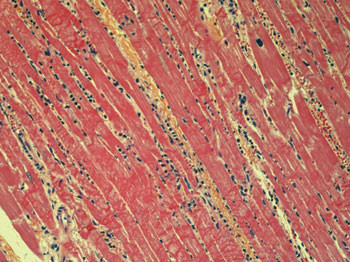

Mikroskopisk undersøkelse av myokard viste tegn til iskemisk skade, med koagulasjonsbånd, stedvis manglende tverrstriping og begynnende infiltrasjon av nøytrofile granulocytter – forenlig med et ferskt hjerteinfarkt, omkring 24 timer gammelt (fig 3). Toksikologiske analyser var negative.